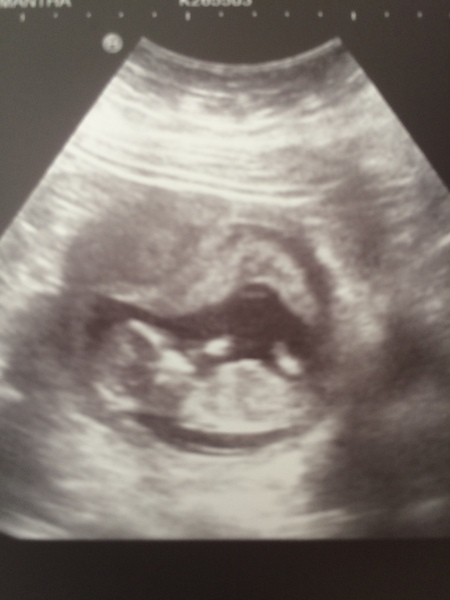

Back from the hospital and everything is good! I was literally only in 10mins in total and I cried my eyes out on the bed as she scanned me and said she could see the heartbeat. They couldn't see any reason for the bleed and Squishy was wriggling around and stretching! Back on Friday for the more detailed dating scan but new measurements put me 2 days ahead! Thank you so so much for all of the support, I'm truly grateful xx